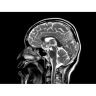

• Комплексная оценка печени — первая в отрасли ИП MR-Touch открывает новые возможности диагностики благодаря способности определять различия в жесткости тканей.

МР-эластография: неинвазивная методика комплектной оценки печени

Пациентам с такими хроническими заболеваниями печени, как фиброз и цирроз, часто требуется регулярное наблюдение гастроэнтеролога. Это может потребовать проведения инвазивных процедур, которые не всегда позволяют получить полную информацию о состоянии печени.

Новая ИП MR-Touch, разработанная компанией GE совместно с клиникой Майо, основана на исследовании печени с помощью акустических волн, в ходе которого выявляются различия в жесткости тканей. Результатом исследования является эластограмма, полное изображение печени. По таким эластограммам радиологи и гастроэнтерологи могут периодически контролировать состояние пациента и принимать информированные решения о терапии. Более того, данная методика открывает новые возможности и позволяет оказывать инновационные услуги имеющимся пациентам и привлекать новых клиентов.